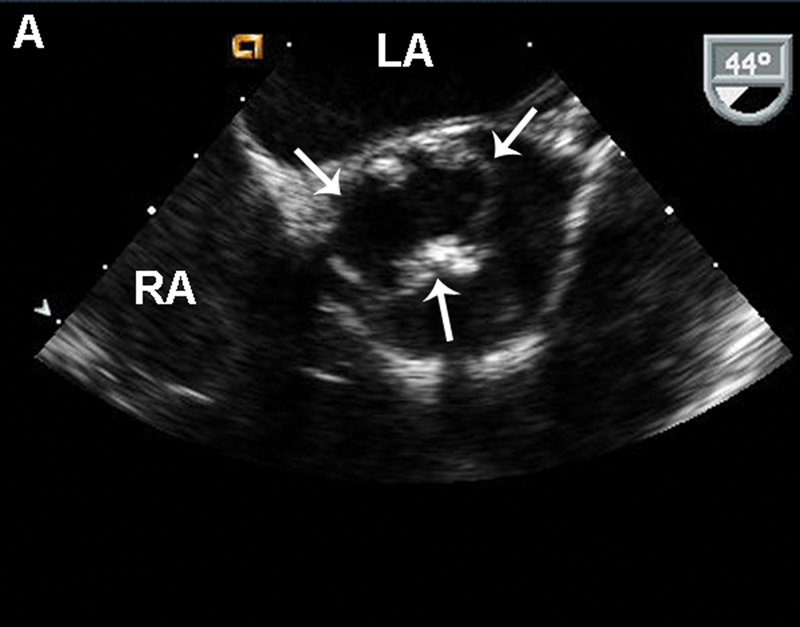

فحوصات تشخيصية لبعض امراض القلب والشرايين التاجية